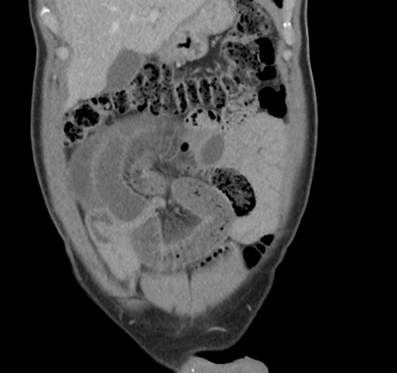

A 55-year-old man presented himself in the emergency department with abdominal pain (VAS 10/10) which appeared suddenly and lasted for a couple of hours. There was no nausea or vomiting. The patient has been hospitalized because of a small bowel obstruction four years earlier which was treated conservatively. In prior patient history there were two incidents where the patient presented himself in the emergency department because of abdominal pain. Once it was interpreted as obstipation the other time as gastritis. There was no history of previous abdominal operations. In the physical examination the abdomen was soft with slightly decreased bowel sounds in the right hemiabdomen and tenderness in the right lower quadrant. Vital signs were normal. Laboratory results showed a white blood cell count of 10.4 G/l and a slighty elevated lactate of 3.6 mmol/l with otherwise normal results. Because of the sudden onset of the pain and the elevated lactate a CT-scan was performed to check for mesenteric ischemia. The scan showed a closedloop obstruction of the small bowel with reduced perfusion and adjoining fluid (Figure 1).

Figure 1: CT-scan that showed a closed-loop obstruction of the small intestines.